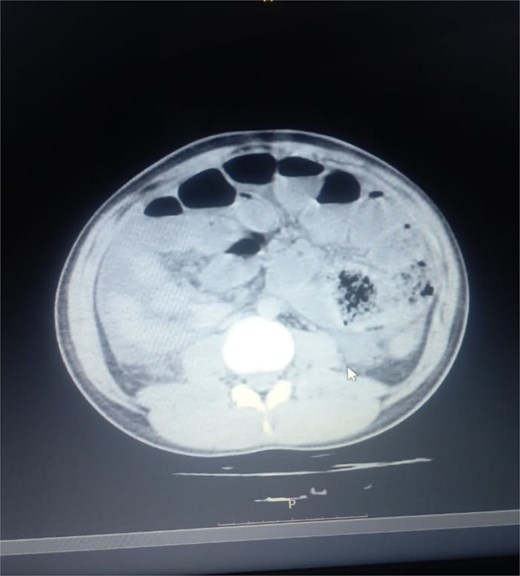

Initial radiographic evaluation with a plain abdominal X-ray confirmed the clinical suspicion of acute intestinal obstruction, demonstrating multiple air-fluid levels and diffuse small bowel dilatation (Fig. 1). To further delineate the underlying etiology, a contrast-enhanced computed tomography (CECT) scan was performed; providing critical diagnostic information it revealed, in the right iliac fossa, a striking encapsulation of the small intestine loops within a sac-like membrane, accompanied by ascites. This constellation of findings formed a pathognomonic cocoon-like structure (Fig. 2). Furthermore, the CECT identified a concurrent gut malrotation, evidenced by a left-sided displacement of the colon (Fig. 3). Laboratory findings showed an elevated total leukocyte count (TLC) of 21 000, indicative of inflammation, while other parameters were within normal limits. The patient underwent an exploratory laparotomy. Intraoperatively, the abdominal viscera were encased within a thick fibrous membrane (Fig. 4), containing ascitic fluid. The membrane was incised, adhesiolysis was performed, and the entrapped small bowel loops were released, and then a kink in the small intestine causing obstruction was identified and corrected. Additionally, the appendix was found to be secondarily involved in the encapsulating process. It was encased in the dense fibrocollagenous membrane, forming an inflammatory mass consistent with chronic serositis and localized fibrosis, rather than a classic acute appendicular phlegmon. Based on this intraoperative assessment that the mass was a manifestation of the cocoon’s chronic inflammation, a simple appendectomy was performed instead of a more extensive right hemicolectomy. This procedure was necessary to achieve complete release of the entrapped bowel, remove this localized inflammatory focus, and obtain a specimen for histopathology to definitively rule out a primary appendiceal pathology as a secondary cause of the peritonitis. Furthermore, ascitic fluid analysis showed no bacterial or mycobacterial growth, ruling out tuberculosis and the histopathological examination confirmed the fibrocollagenous nature of the membrane. The patient recovered well postoperatively and was discharged on the sixth day with advice for a follow-up after 2 weeks. At the follow-up visit, he reported no symptoms, and abdominal imaging confirmed the absence of obstruction. Histology further confirmed the benign fibrous nature of the membrane, with no signs of malignancy.

Axial CT demonstrating key pathological features. This contrast-enhanced axial view shows the colon displaced to the left side of the abdomen, confirming the presence of gut malrotation. The centrally clustered small bowel loops are seen encased in a dense sac, forming the characteristic cocoon structure that is pathognomonic for abdominal cocoon syndrome.